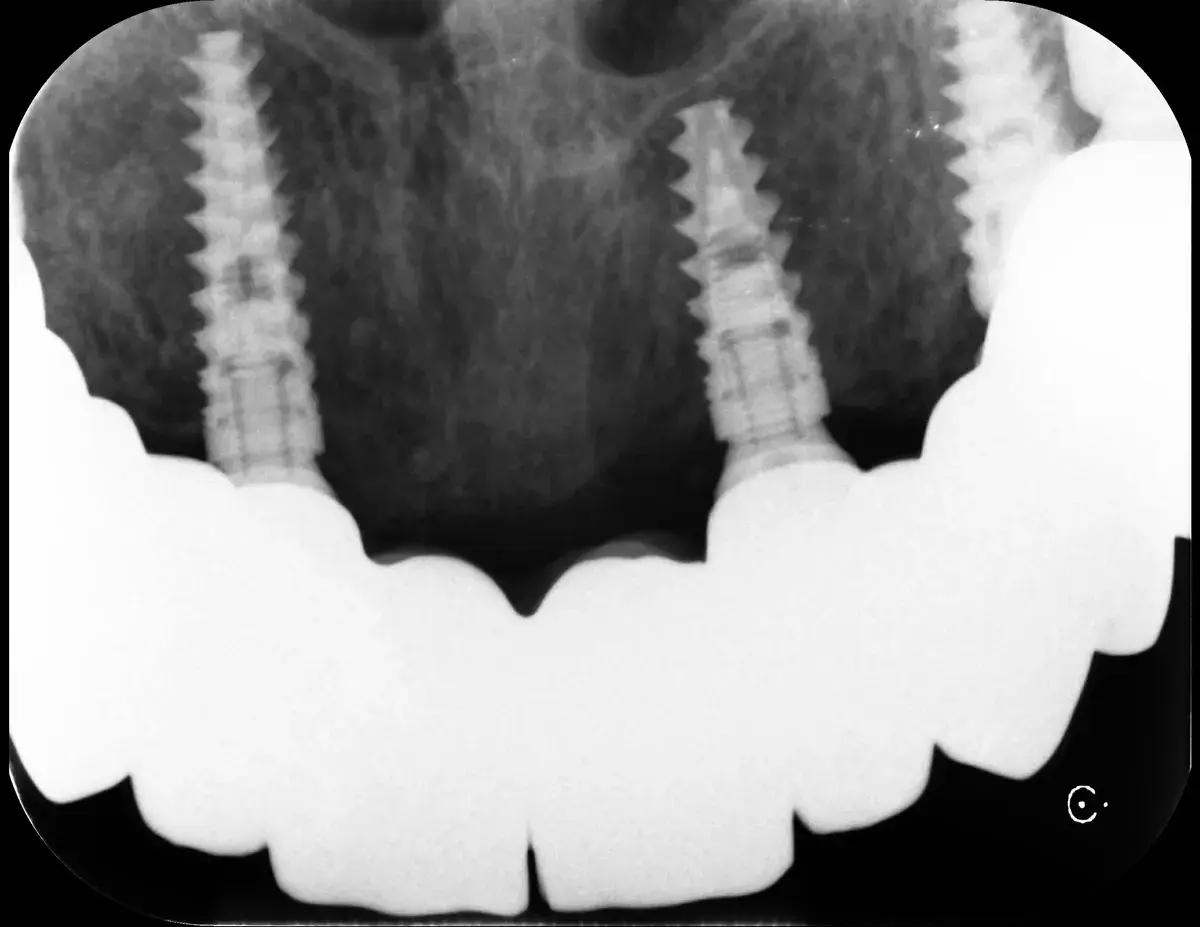

Caso clinico di carico immediato su rialzo crestale del seno mascellare con espansori. Espansione apicale, stabilità >50 Ncm, provvisorio immediato e co...

Scopri i principi fondamentali per il posizionamento corretto degli impianti e l'uso di connessioni coniche e MUA, per prevenire la peri-implantite e l'...

Un impianto mal posizionato causa perdita ossea di 0,25 mm ogni 10° di errore. Come riconoscere il problema, quando si può correggere e quando va rimosso.

Bone-level, tissue-level, connessione conica: la profondità corretta cambia con il tipo di connessione. Perché sbagliarla causa riassorbimento osseo.